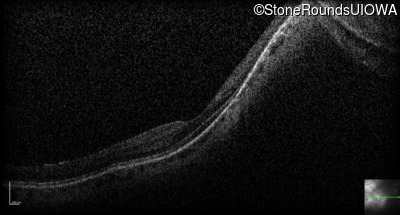

Optical Coherence Tomography - Left - 20/25 +2

Exemplar / OCT Stack